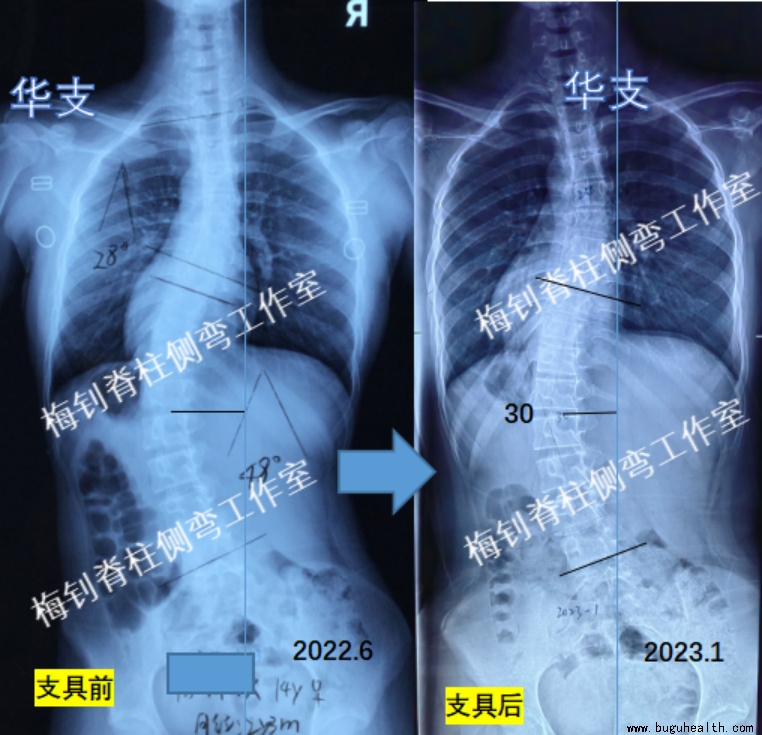

案例1

很多家长,发现孩子侧弯时,往往已经过了最佳的干预时期,但家长总会想尽一切办法,期望给孩子做出最好的选择。这个案例的家长也一样,孩子父亲是急诊科医生,发现侧弯时,孩子15周岁,生理期已经来了2年多,腰椎主弯曲已经达到了48度,家长利用职业便利带孩子遍寻名医,但所有的专家给出了一致的答案,建议手术!但家长仍然不死心,于2022年6月底来我工作室尝试支具干预。

2023年1月,孩子穿戴支具已经7个月,身高增长2cm,体重增加3.8kg,脱支具2天后拍片,主弯曲由48度降为30度。面对这样的结果,家长非常满意,我们也感到甚是欣慰,但同时,后期的发展仍然存在很多不确定性,对于生长末期的大度数侧弯,一般还是建议手术的。我们的案例也将继续跟踪,及时分享给大家参考。